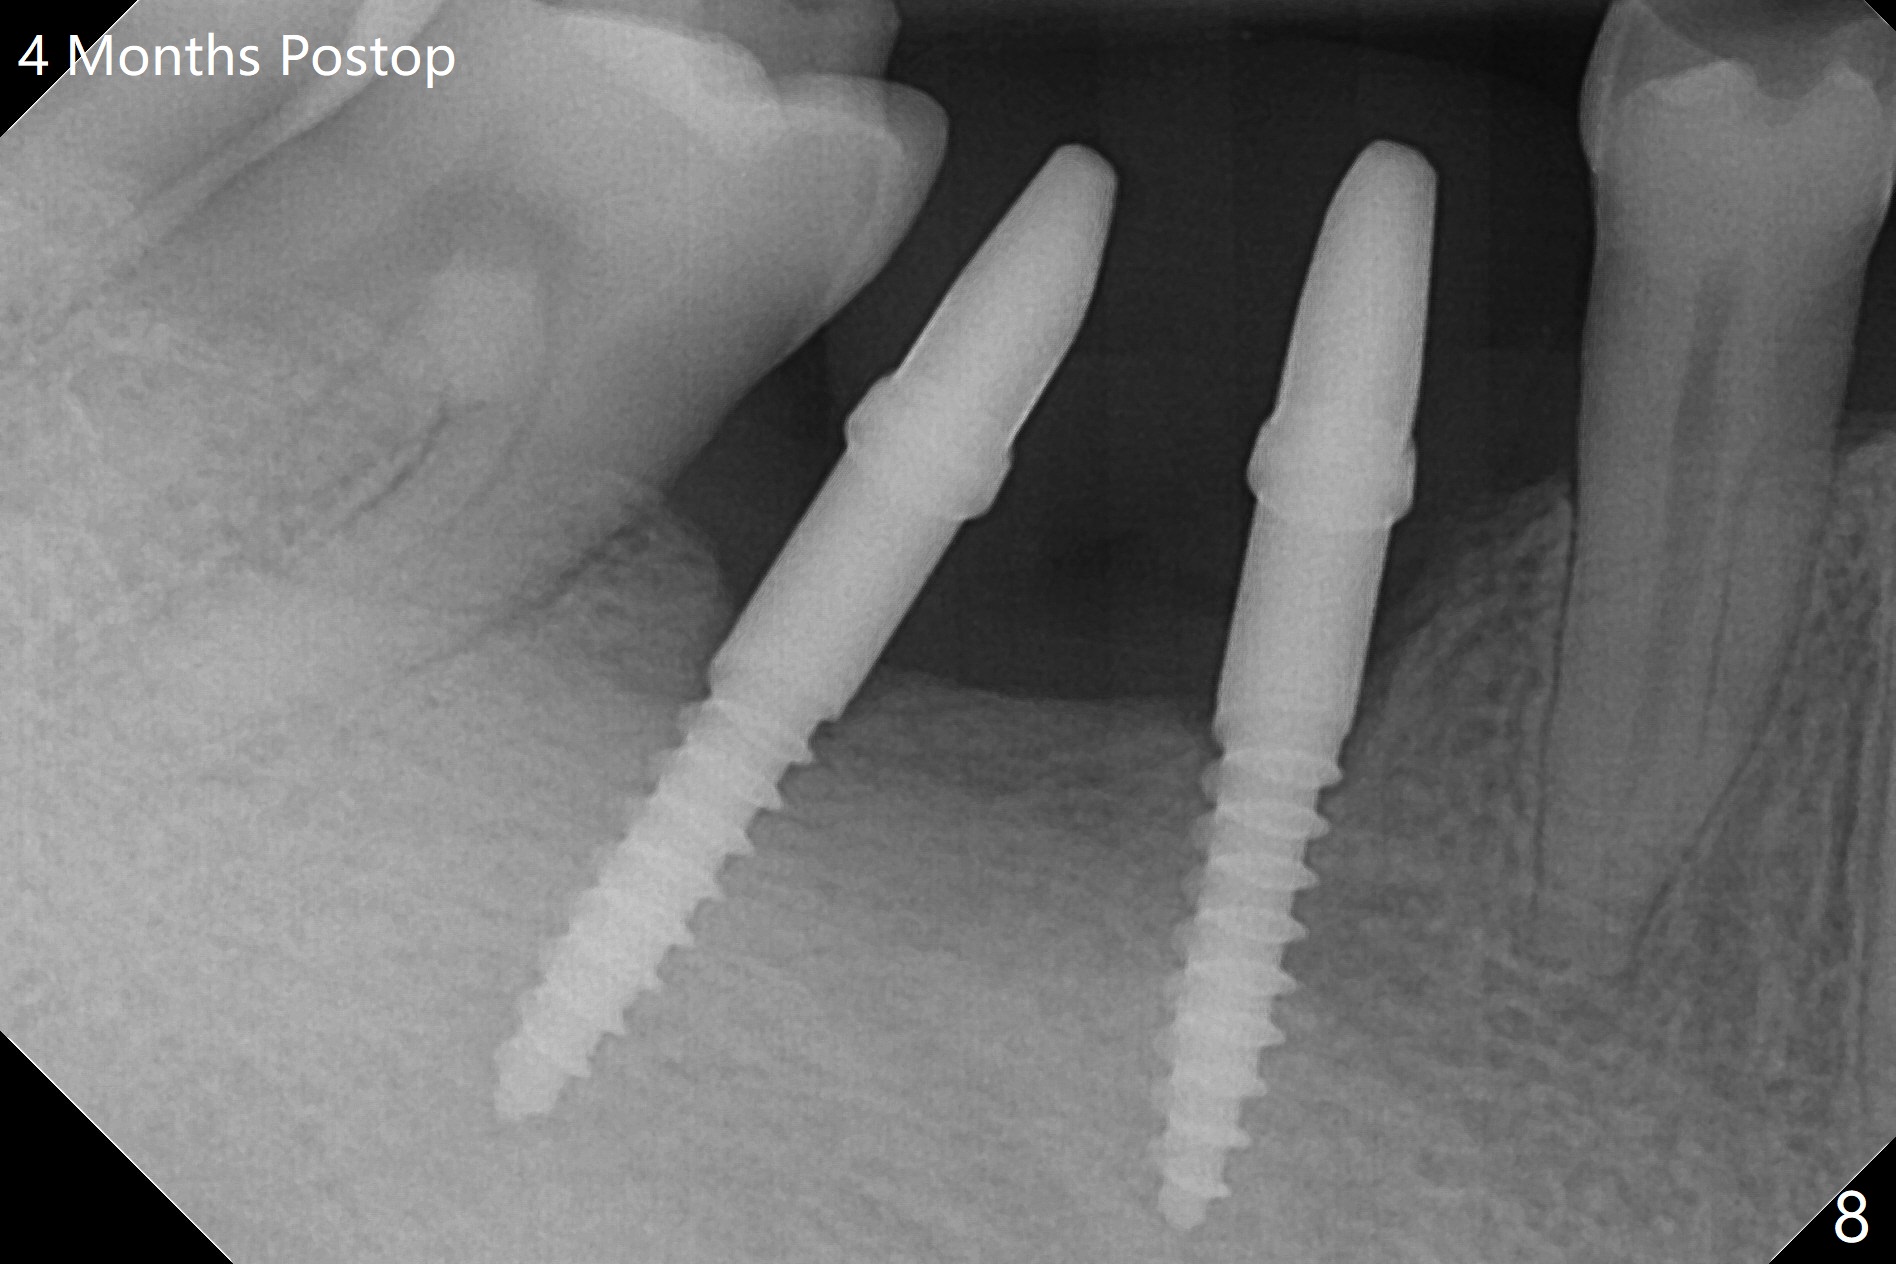

After initial osteotomy using 2.2 mm drill for 10 and 11.5 mm at #29 and 30, respectively, the guide is removed for re-insertion of drills and PA (Fig.1). The osteotomy at #29 is found lingually and in the nonkeratinized gingiva with mild laceration (wish incision to be made before osteotomy); the osteotomy is established a little lingual at #29 (Fig.2) and more or less in the middle of the narrow ridge and #30 (Fig.3). Lindamann bur is used to move #29 osteotomy buccally. A 1.5 mm drill is used to increase the depth free hand before placement of 2.5x10(4) mm 1-piece implants (Fig.4). After adjustment of the implant depth (Fig.5), CT is retaken, which shows proper implant placement (Fig.6,7). Probably due to good oral hygiene, the gingiva around the implants appears to be keratinized 4 months postop (Fig.8). After abutment preparation for margin and parallelism, impression is taken (Fig.9). When the permanent crowns are temporarily cemented, the large gingival embrasure is noted (Fig.10,11). The latter could be reduced by modifying the provisional in the healing stage. In fact the crown at #29 dislodges 2 days post cementation because lingual (Fig.12) and distal (Fig.13) placement. A surgical stent should have been fabricated from RPD for free hand placement!